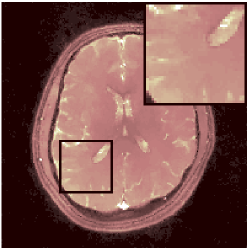

Two sets of experiments were conducted here: first, we used the 2D and 3D acquisition sequences for scanning a healthy volunteer’s brain (real-world acquisitions). Figures 6 and 7 display the parametric maps reconstructed from 2D spiral and radial readouts. We computed the T1, T2 and proton density (PD) maps using baseline reconstruction algorithms ZF, VS, LR, FLOR, AIR-MRF and our proposed LRTV. While baselines use DM either for quantitative inference or also during reconstruction (i.e. AIR-MRF), we further compare the DM-free LRTV’s performance when cascaded to DM, KM and MRFResnet for quantitative inference. For the 3D spiral acquisitions we compared LRTV and its closest competitor VS in Figure 8. Outcomes from other tested algorithm are displayed in the supplementary materials (Figure S5). Since FLOR does not use dimensionality-reduction, our system ran out of memory during 3D reconstruction; hence results are not reported in this case.

VI-E1 Discussion

The LRTV-DM and LRTV-MRFResnet perform on par, and both outperform all tested baselines for reconstructing T1, T2 and PD maps in all acquisition schemes. This can be observed both visually in Figures 6, 7, 8, S2 and S3, and quantitatively in Table IV across all tested metrics. Other baselines were unable to successfully remove the under-sampling artefacts in TSMIs, and these errors propagated to the parameter inference phase and resulted in inaccurate maps. Temporal-only priors incorporated within LR are shown insufficient to regularise the inverse problem and LR sometimes (e.g. 2D spiral acquisitions) can admit solutions with even stronger artefacts than the model-free ZF baseline. This issue was previously studied for other non-Cartesian MRF readouts that similar to our spiral/radial trajectories, miss to sample the corners of the k-space in all timeframes (see section 2.2.2 and figure 2 in [19]). In the absence of reference for the k-space corners information, the LR iterations despite minimising the objective can converge to solutions with high-frequency artefacts, as visible in the computed maps. This highlights the need for adding an appropriate spatial-domain regularisation. FLOR reduces the LR’s artefacts but this improvement is limited because the suggested nuclear norm penalty does not incorporate an explicit spatial regularisation. Further for reducing artefacts, FLOR can introduce an undesirable bias in the computed T1/T2 maps e.g. see error maps in Figures S2 and S3. The non model-based VS baseline incorporates spatial regularisation and results in spatially smoother maps than ZF and LR, but it is unable to output artefact-free images. Further and consistent with our in-vitro experiment, we observe that VS overestimates the T2 values (e.g. in White and Grey matter regions) in tested 2D acquisitions i.e. the spatial regularisation trades off agains the quantification accuracy. The model-based AIR-MRF adds spatial regularisation through 2D/3D low-pass Gaussian filters however this trades off the sharpness of the computed maps and can increase the errors at the tissue boundaries (we searched Gaussian spreads that keep the blurs and high-frequency artefacts minimal). For our acquisition readouts, Gaussian filters performed better than disk filters of [19] for avoiding strong Gibbs artefacts. On the other hand, the spatiotemporally regularised LRTV greatly improves the TSMI reconstructions i.e. 4 dB enhancement compared to the closest competitor baseline (Table IV). This enables computing accurate and aliased-free multi-parametric inference using DM or the DM-free learning-based alternative MRFResnet as visible in Figures 6, 7, 8, S2 and S3. MRResnet and DM score competitive quantitative inference results i.e. T1 and T2 MAPE less than 5% and 9%, respectively (Table IV). KM also outputs comparably accurate T1 maps, however this shallow learning model despite having a model size larger than MRFResnet, is unable to learn accurate T2/PD quantification and it results in poor estimated maps, consistent with our observations in section VI-C.